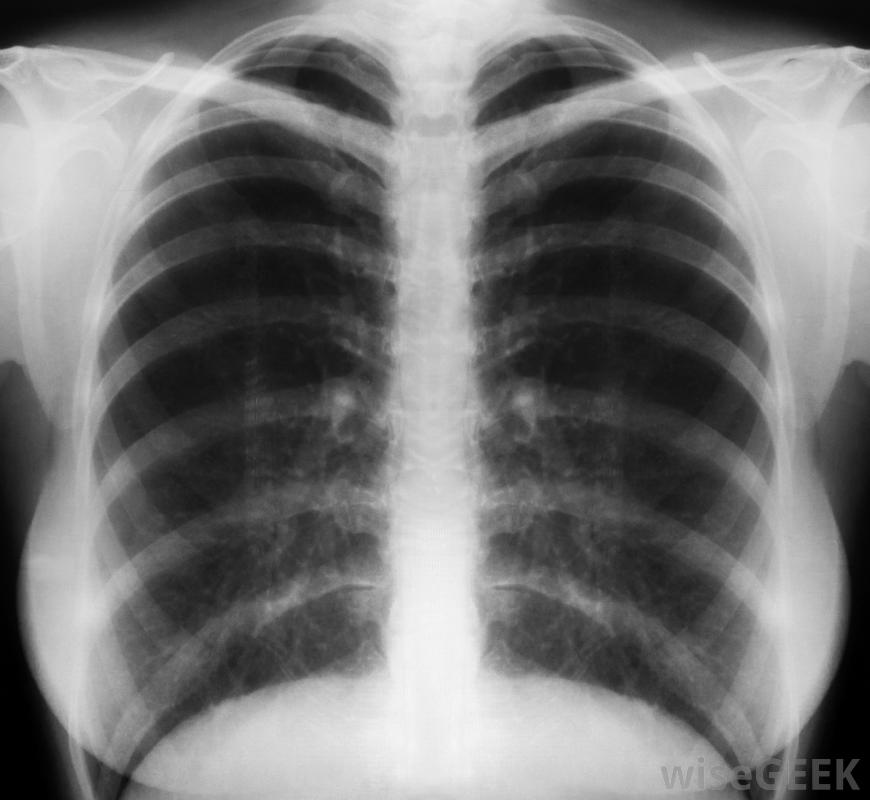

胸部x光片对消除肺炎比确认支气管炎更有效成人急性和慢性支气管炎的症状包括不停的咳嗽,可能产生清、白、绿或黄灰色的痰。其他症状包括疲劳和低热。呼吸急促,喘息和胸痛也可能发生。支气管炎患者可能只经历一到两种症状,而不是所有症状除了这些症状外,慢性支气管炎患者还可能出现持续咳嗽,这种咳嗽通常在早晨或潮湿的天气更为严重,粘液产生,个体呼吸困难。成人支气管炎的治疗有助于缓解症状。推荐的治疗方法通常包括多喝水,充分休息,戒烟并服用阿司匹林、对乙酰氨基酚或布洛芬,以降低发热和减轻疼痛。从加湿器或热水淋浴中呼吸蒸汽可以帮助咳嗽更有效,非处方的止咳药可以帮助停止咳嗽,让患者入睡。含有愈创木酚的祛痰止咳药有助于缓解咳嗽,使其更有效,并有助于排出体内的粘液。医生可以开处方药,如抗生素或处方强效咳嗽药。

成人支气管炎可能会出现轻微的发烧、疲劳和胸痛。医生通过评估患者的症状并用听诊器听他们的胸部来诊断成人支气管炎。在某些情况下,医生可能会要求咳出的粘液样本要做细菌检查x光片通常用来排除肺炎,而不是确诊支气管炎。